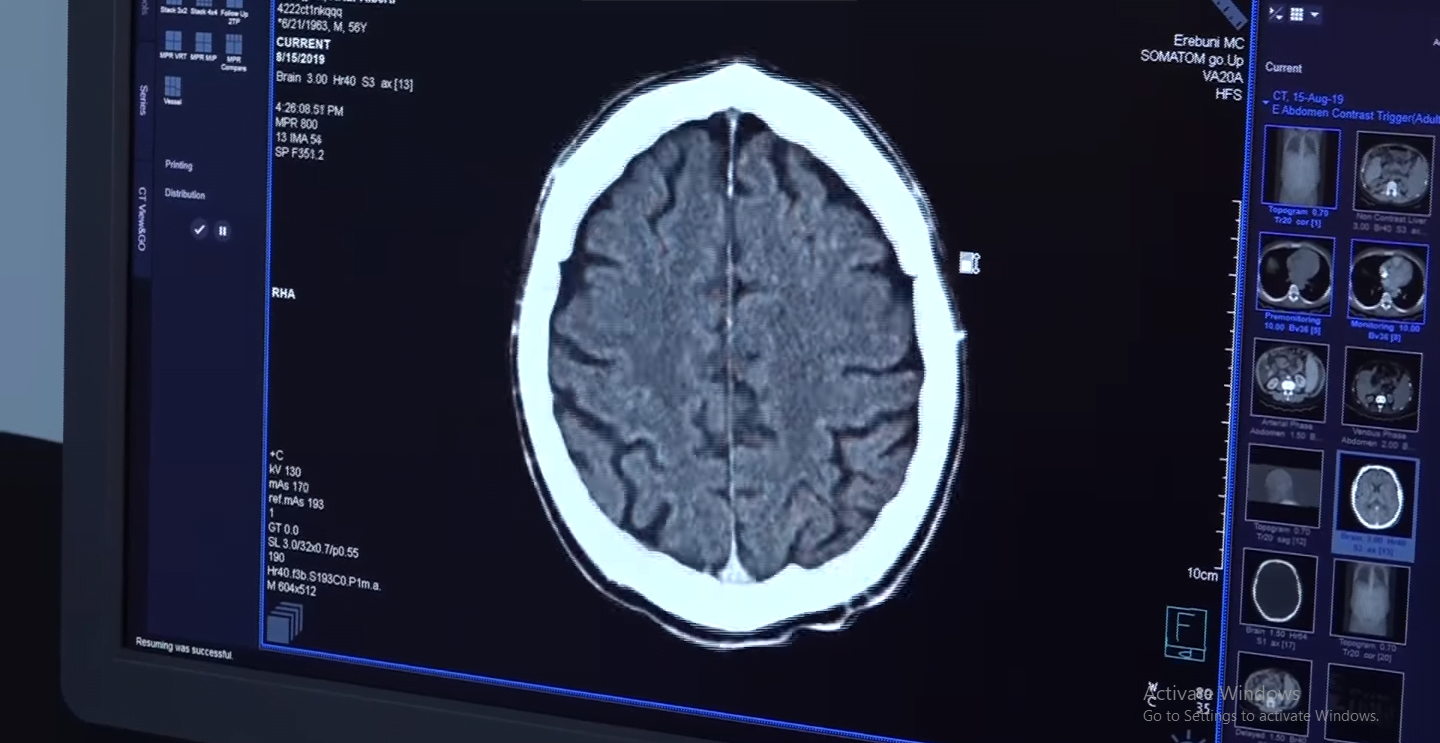

Գլխուղեղի սուր իշեմիկ կաթվածի ծրագրով անվճար բուժօգնություն է ստացել 180 քաղաքացի (ՏԵՍԱՆՅՈՒԹ)

Գլխուղեղի սուր իշեմիկ կաթվածի ծրագրով անվճար բուժօգնություն է ստացել 180 քաղաքացի, փրկվել է 151 կյանք։ Այս մասին հայտնում է ՀՀ կառավարության ֆեյսբուքյան պաշտոնական էջը: Անվճար բուժօգնություն ստացածների 50 տոկոսը Երևանից է, մնացածը մարզերից: Ծրագրի շնորհիվ կանխվում է նաև հաշմանդամություն ձեռք բերելու վտանգը: https://www.facebook.com/armgovernment/videos/370350556980495/?v=370350556980495

Փետրվարի մեկից գործում է բնակչությանը պետության կողմից երաշխավորված անվճար բժշկական օգնության և սպասարկման շրջանակներում գլխուղեղի սուր և/կամ ենթասուր իշեմիկ կաթվածների թրոմբոլիտիկ բուժման և մեխանիկական թրոմբէկտոմիայի ծրագիրը: Կաթվածի անհետաձգելի վարման ծառայությունների կազմակերպման հիմքում պացիենտի մոտ «գլխուղեղի սուր և/կամ ենթասուր իշեմիկ կաթված» ախտորոշումն է: Այսինքն` պետական պատվերը գործում է գլխուղեղի իշեմիկ կաթվածի կլինիկական նշանների ի հայտ գալու…

Առողջապահության նախարար Արսեն Թորոսյանը մասնակցել է Հայաստանում գլխուղեղի կաթվածի բուժման և կառավարման համակարգող խորհրդի անդրանիկ նիստին, որտեղ ներկա էին խորհրդի նախագահ` «Էրեբունի» ԲԿ նյարդաբանության ծառայության ղեկավա Նունե Եղիազարյանը, Բոստոնի Բժշկական համալսարանի նյարդաբանության պրոֆեսոր Վիկեն Բաբիկյանը, Կանադայի Ալբերտայի համալսարանի նյարդավիրաբուժության դոցենտ Միքայել Սքոն Մուրաթօղլուն և մի շարք այլ մասնագետներ: Քննարկման հիմնական թեմաներն էր կաթվածի համապարփակ կենտրոնների…